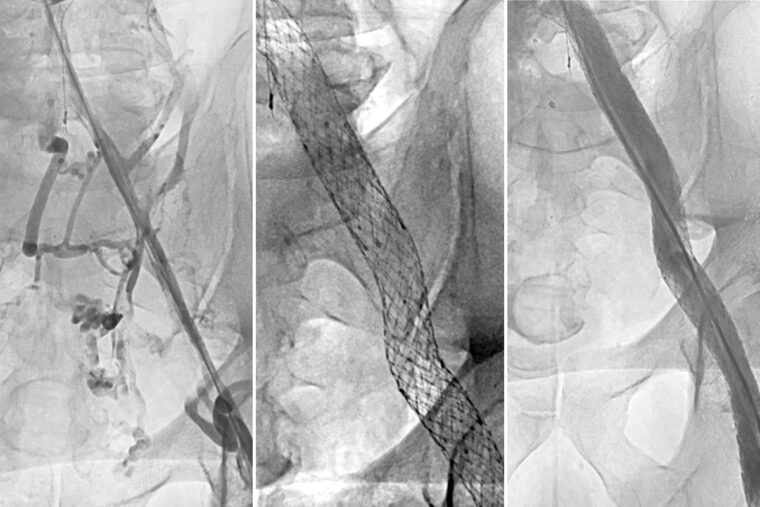

Opening a narrowed vein damaged by deep vein thrombosis can effectively treat an often painful complication following a blood clot, according to a major clinical trial co-led by WashU Medicine. The left panel shows a narrowed vein in the thigh of a patient with severe post-thrombotic syndrome. A stent is placed in the vein (center panel), which then enables better blood flow (right). (Image courtesy of Suresh Vedantham)

The study enrolled 225 patients at 29 sites across the U.S. who had been treated for deep vein thrombosis for at least 3 months and had blockage of the iliac vein (a major vein in the pelvis) causing substantial disability. Patients were chosen at random to receive either a stent — a mesh tube inserted into the vein to reinforce and expand it — plus standard treatment with compression and blood-thinning medications, or standard treatment alone. A stent is placed in a two-to-three-hour operation that requires only tiny incisions.

At the start of the study, 93% of participants met the clinical criteria for severe post-thrombotic syndrome. Six months after treatment, just 40% of patients who received the stent still experienced severe post-thrombotic syndrome, compared to 61% in the standard care group.

Patients with stents also reported improved symptoms in the veins of their legs and overall quality of life following the procedure compared with those on standard treatment. On a 100-point quality of life scale, those who received the stent scored 14 points higher, a large improvement.